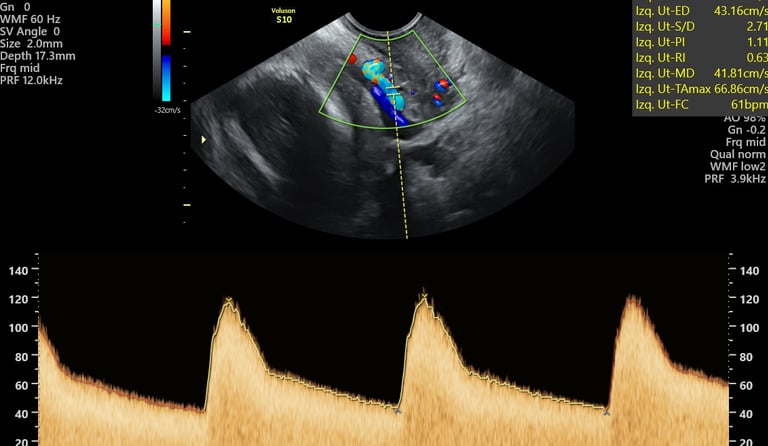

ecografía de crecimiento Doppler

24 - 40 semanas